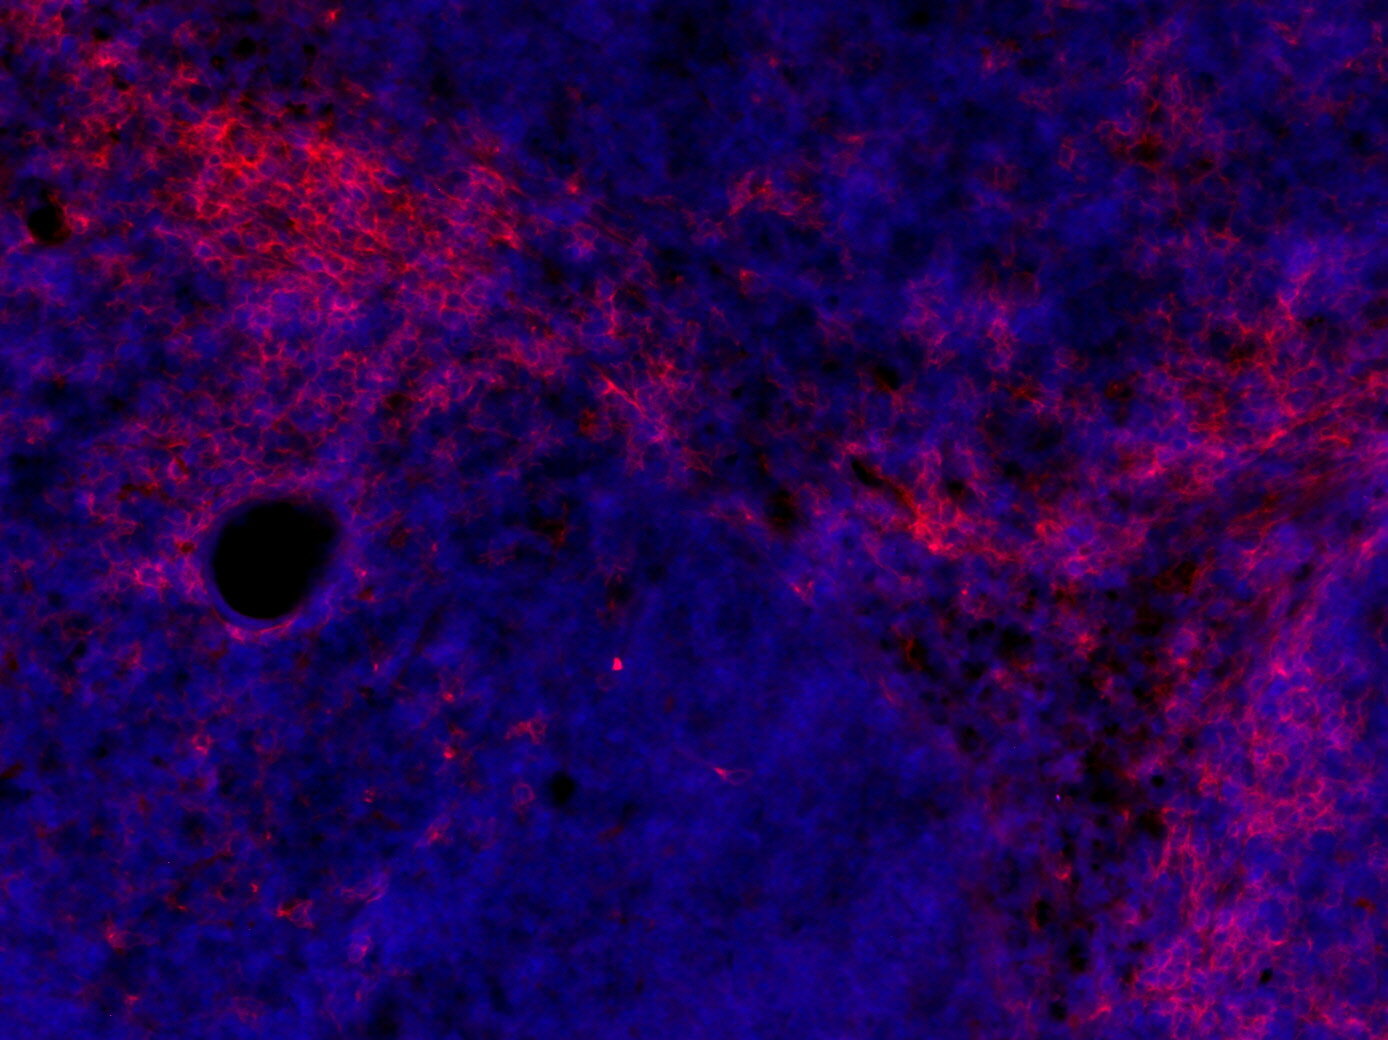

CD11c positive cells in FFPE mouse ileum section

IHC: 1 : 500 (see remarks) gallery

IHC-P: 1 : 50 up to 1 : 100 gallery

IHC-Fr: 1 : 500 (see remarks) gallery

Immunohistochemistry (IHC) on 4% PFA perfusion fixed tissue with 24h PFA post fixation. Immunoreactivity is usually revealed by fluorescence or a chromogenic substrate. Some antibodies require special fixation methods or antigen retrieval steps. For details, please refer to the ”Remarks” section.

Immunohistochemistry (IHC-P) of formalin fixed, paraffin embedded (FFPE) tissue (some antibodies require special antigen retrieval steps, please refer to the ”Remarks” section). Immunoreactivity is usually revealed by fluorescence or a chromogenic substrate.

Immunohistochemistry on fresh frozen (IHC-Fr) cryo-tissue-sections. In contrast to standard PFA perfusion fixed tissues, fresh frozen cryo-tissue-sections can be variably postfixed with alcohols, acetone or PFA. Alcohol or acetone fixation is e.g. of advantage for antigens masked by PFA crosslinking. For recommended postfixation, please refer to the ”Remarks” section. Immunoreactivity is usually revealed by fluorescence or a chromogenic substrate.

IHC: Antigen retrieval with citrate buffer pH 6 is required.

IHC-Fr: 4% formaldehyde/PFA fixation is recommended.